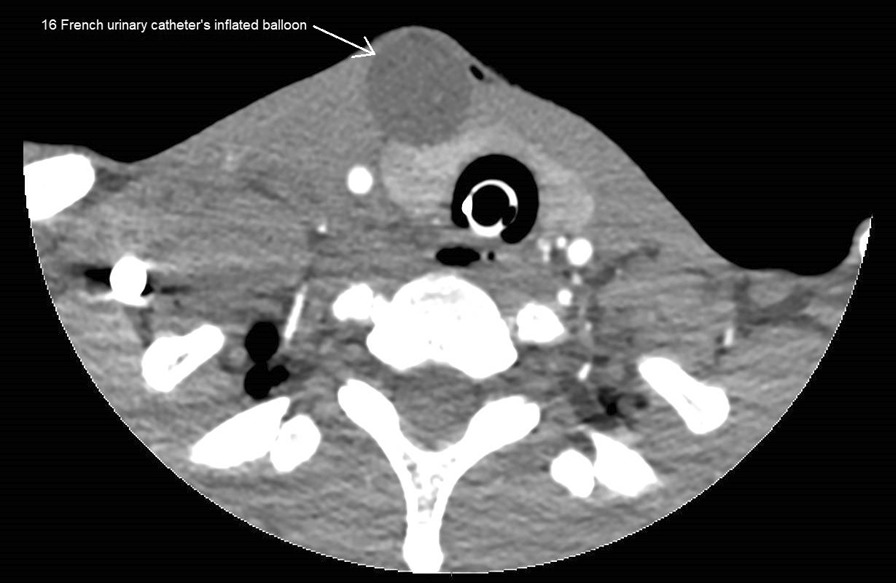

The use of Foley catheter tamponade for bleeding control in penetrating injuries.

Foley导管填塞在穿透性损伤出血控制中的应用。